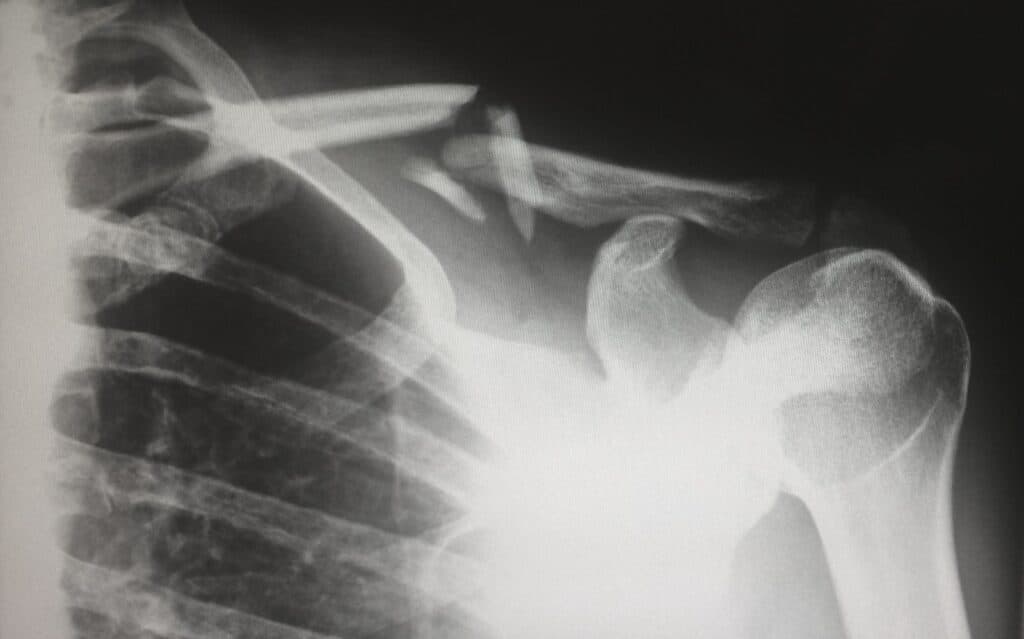

Sempre que lá entro vou a reclamar da vida. Ora traz um pé amassado, um braço inchado ou qualquer outra marca de guerra resultante de futeboladas disputadas com temperaturas negativas. Certo como o destino, vou ter de passar pelo raio-x, e isso num hospital que parece um estaleiro significa que vou andar a fazer os 800 metros obstáculos.

Começo num edifício para dar entrada da ocorrência. Uma espécie de recepção e primeira triagem. Já conheço a cantiga de cor e segue-se, por norma, a caminhada para o bloco “lá de baixo”, onde está a radiologia. Por fim, atravesso outras duas ruas para que o puto seja visto por um médico, num terceiro edifício, aí a uns 600 metros de distância. ↓